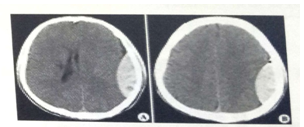

试题2:男,44岁。头部外伤12小时。结合CT片,此诊断为(2分)

答案:C

影像学2